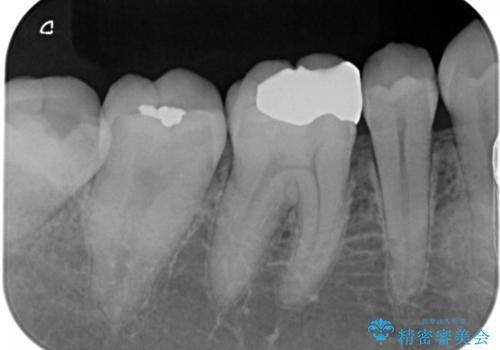

- 銀歯のやり替えをご希望された患者様です。手前の歯にもプラスチックと歯の間に虫歯が出来ていたため、両方とも適合の良いセラミックで補綴しました。

適合不良の補綴物は二次的な虫歯発生のリスクが高まります。

自費診療で用いられる材料は保険適応の材料に比べて、より精密で適合の良い被せ物作ることができるため、長期的な虫歯のリスクを大幅に減らすことが可能です。